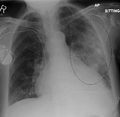

- Normal AP CXR

Normal lateral CXR

AP CXR showing left lower lobe pneumonia associated with a small left sided pleural effusion

AP CXR showing right lower lobe pneumonia

AP CXR showing pneumonia of the lingula of the left lung

Right upper lobe pneumonia as marked by the circle.- Left upper lobe pneumonia with a small pleural effusion.

- Right lower lobe pneumonia as seen on a lateral CXR